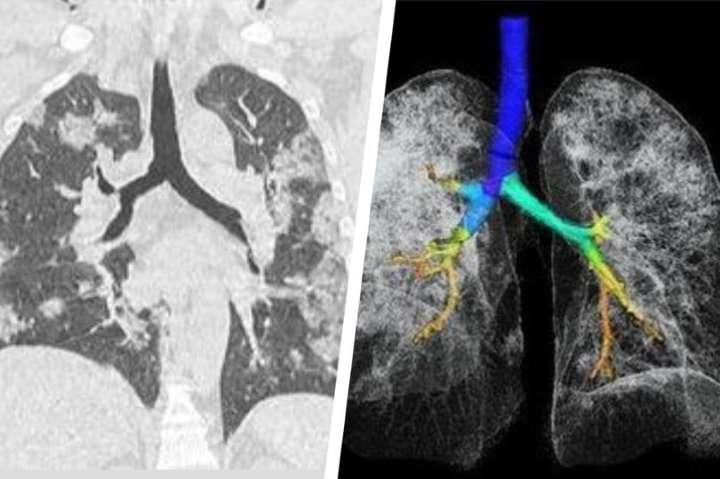

Mai multe studii arată că persoanele contaminate cu noul coronavirus ar putea rămâne cu probleme pulmonare pentru tot restul vieţii. Primele avertizări în acest sens au venit din China, în luna martie, când pandemia abia începea în Europa.

Un studiu relativ mic raporta că din 70 de pacienți care au dezvoltat pneumonie 66 au rămas cu leziuni pulmonare. Aceste leziuni se manifestau în moduri diferite de la pacient la pacient și păreau să afecteze fie alveolele pulmonare, fie țesuturile din jurul alveolelor.Un alt studiu din Hong Kong descria cum, din 20 de pacienți internați pentru Covid-19, jumătate nu și-a recăpătat în totalitate funcția pulmonară.Mai mult, în vreme ce SARS și MERS (coronavirusuri înrudite cu virusul care cauzează COVID-19) păreau să afecteze un singur plămân, aici ambii plămâni erau afectați.Yuhui Wang, unul dintre autorii studiului din China, menționa că se așteaptă ca o parte din aceste leziuni să se vindece în timp, dar nu a trecut suficient de mult timp pentru a avea o certitudine în această direcție.Cea mai mare problemă este că o parte a leziunilor par a fi permanente, în special cele cauzate de cicatrizarea țesutului pulmonar. Un răspuns prea puternic al sistemului imunitar (așa-numita furtună de citokine) ar cauza aceste leziuni. Cei care sunt în special expuși acestei probleme sunt cei mai în vârstă sau cu probleme preexistente de sănătate.Totodată, într-un interviu acordat ziarului olandez AD și tradus de NLTimes, pneumologul Leon van den Toorn spunea că "mii de olandezi ar putea avea leziuni pulmonare permanente" cauzate de COVID-19.Conform lui van den Toorn, dintre cei 1.200 de pacienți care au fost internați la terapie intensivă, peste 100 au plecat acasă cu leziuni. De asemenea, adaugă doctorul olandez, cam jumătate din cei 6.000 de oameni care au fost spitalizați vor rămâne cu simptome pulmonare ani în șir.Aceste simptome includ dificultăți sporite în respirație, în special la depunerea de eforturi ușoare, care, în mod normal, nu ar cauza probleme. Pot indica probleme remanente și pot duce la scăderea oxigenării sângelui, care ar putea cauza alte probleme de sănătate. Medicii din Marea Britanie au tras concluzii similare, atrăgând atenția că mulți pacienți de COVID-19 ies din spital cu probleme pulmonare.Ce trebuie să știm?Nu e deloc surprinzător că această infecție cauzează probleme cronice pentru supraviețuitori. În cazul MERS, peste o treime din cei care au avut probleme pulmonare nu-și reveniseră nici după câteva luni, iar probleme similare au fost raportate și la SARS.Pentru cei care au avut această boală – și pentru doctorii care i-au supervizat – este important să monitorizeze apariția acestor simptome. Pacienții pot nota simptomele observate, iar într-un cadru medical se pot face radiografii pentru a confirma potențialele leziuni.Doctorii olandezi au lansat deja o platformă prin care vor să urmărească evoluția problemelor cronice pulmonare apărute ca urmare a infecției cu noul coronavirus și e un model pe care am putea să-l urmăm.Pentru noi toți, e un semnal de alarmă: de multe ori ne uităm la o boală și la câți oameni omoară, dar ignorăm suferința mai amplă provocată din cauza bolii.sursa: www.libertatea.ro